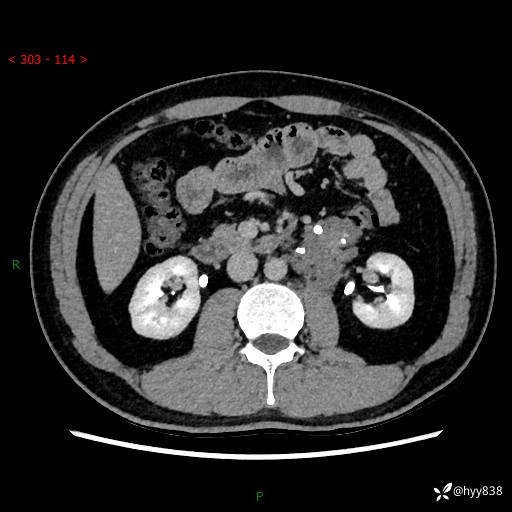

现病史:患者3月余前检查发现左侧腹膜后占位,大小约3.7*4.9cm,平素无腰疼,无肉眼血尿,无尿频尿急等不适,当时未特殊处理,在门诊复查CT提示左侧腹膜后占位,门诊拟“左侧腹膜后占位”收入院。 起病以来,患者精神佳,饮食、睡眠良好,大小便正常,体力体重无明显变化。

腹膜后CT平扫+增强